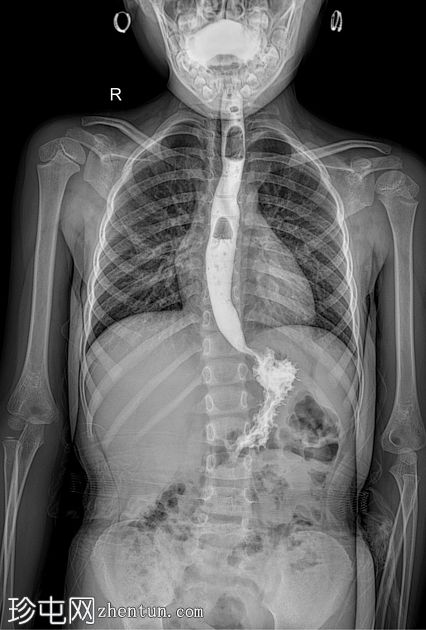

荧光透视

4.jpeg

斜向

食管体扩张,远端食管平滑收窄,呈现经典的鸟嘴状或鼠尾状外观

扩张食管内可见气液平面

造影剂进入胃排空延迟

荧光透视钡餐检查显示食管扩张,胃食管连接处平滑收窄,造影剂进入胃延迟。虽然这些特征提示贲门失弛缓症,但并非其特征性表现,尤其是在儿童中,因为下食管括约肌狭窄有时可视为正常变异。

贲门失弛缓症在儿科人群中并不常见,但对于年龄较大且存在非特异性上消化道症状的儿童,例如吞咽固体和液体食物困难、反流、体重下降或反复食物潴留,则应考虑该病。可能支持诊断的影像学征象包括:

食管均匀扩张

原发性蠕动消失

排空延迟

食管远端平滑收窄

荧光透视被认为是评估疑似贲门失弛缓症的一线影像学检查方法。